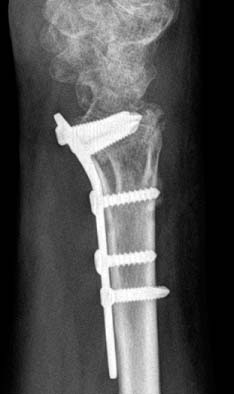

Fig. 8

This juxtaarticular plate is fixed distal to the transverse ridge.

Fig. 8 This juxtaarticular plate is fixed distal to the transverse ridge.